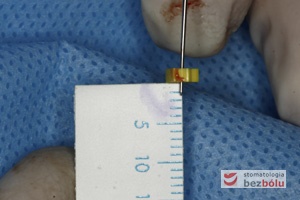

Mapowanie kości – diagnostyka grubości błony śluzowej przy użyciu instrumentu endodontycznego

Mapowanie kości – diagnostyka grubości błony śluzowej przy użyciu instrumentu endodontycznego

Sondowanie kości – kalibrowany marker pozwala na obliczenie gęstości pierwszego nawiertu